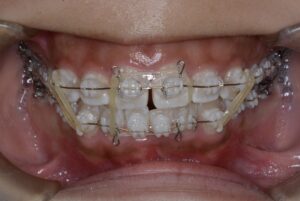

親知らずによって持ち上げられていた臼歯部を圧下していく。臼歯部を圧下しつつ、

前歯を咬合させるように顎間ゴムで力を少しずつかけていく。